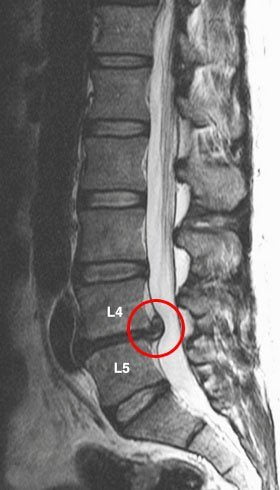

Главным виновником боли в спине является остеохондроз. Локализация болезненных ощущений будет зависеть от того, какой участок позвоночника патологически изменен. Чаще всего страдает поясничный отдел позвоночника. При этом возникает постоянная ноющая боль внизу справа или слева. При поражении грудного отдела, болезненные ощущения могут локализироваться выше поясницы или под лопаткой.

При развитии осложнений остеохондроза (защемление нервов, их воспаление — радикулит) боль приобретает другой характер.

Развивается проецируемый болевой синдром – болезненные ощущения иррадиируют по ходу вовлеченных нервных окончаний (в руку, в ногу). Такая боль может иметь постоянный характер (люмбалгия, торакалгия) или в виде прострела (люмбого, торакаго).

Ведущий симптом всех патологий позвоночника — боль в спине. Ее появление справа типично для одностороннего ущемления нервного корешка. Это часто происходит при остеохондрозе шейно-грудного, грудного, поясничного, пояснично-крестцового отделов позвоночника. Особенно часто боли возникают при его уже развившихся осложнениях: протрузии, межпозвоночной грыже, дискогенной миелопатии, корешковом синдроме.

Повреждение дисков, позвонков, а особенно сдавление спинномозговых корешков редко проявляются четко локализованными болями. Они распространяются на рядом расположенные участки тела, иррадиируют в руки, ноги, бока.